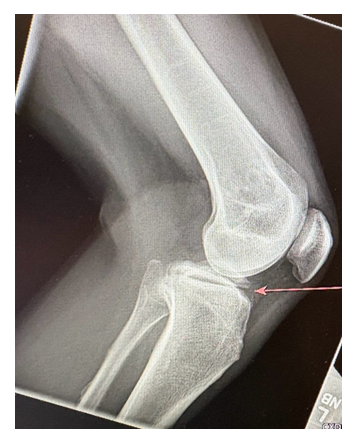

Radiography of the knee revealed a transverse fracture through the proximal tibial metaphysis, with minimal soft tissue swelling and no joint effusion. A non-contrast CT was obtained for further evaluation, which confirmed fractures of both the distal femur and proximal tibia, along with a moderately-sized hemarthrosis. A mildly displaced avulsion fracture was identified at the anterolateral tibia.

Magnetic resonance imaging revealed a tibial eminence fracture fragment measuring 4.2 cm x 4.4 cm, involving the attachment sites of both the anterior and posterior cruciate ligaments.